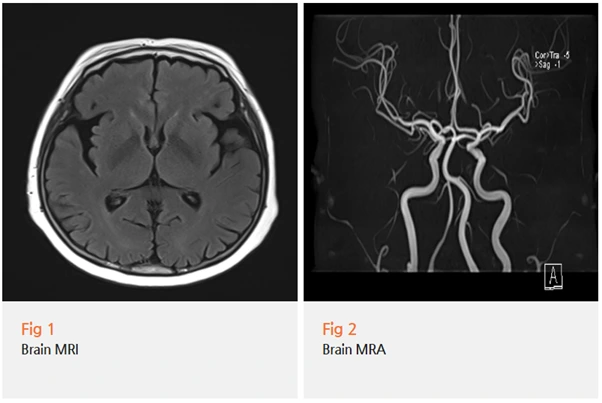

그래서 뇌 MRI와 MRA를 포함한 정밀 검사를 진행했어요.

검사 결과, 다행히 뇌경색이나 종양 같은 급성 문제는 없었고요.

임상 증상과 검사 소견을 종합했을 때

파킨슨병으로 진단할 수 있었어요.